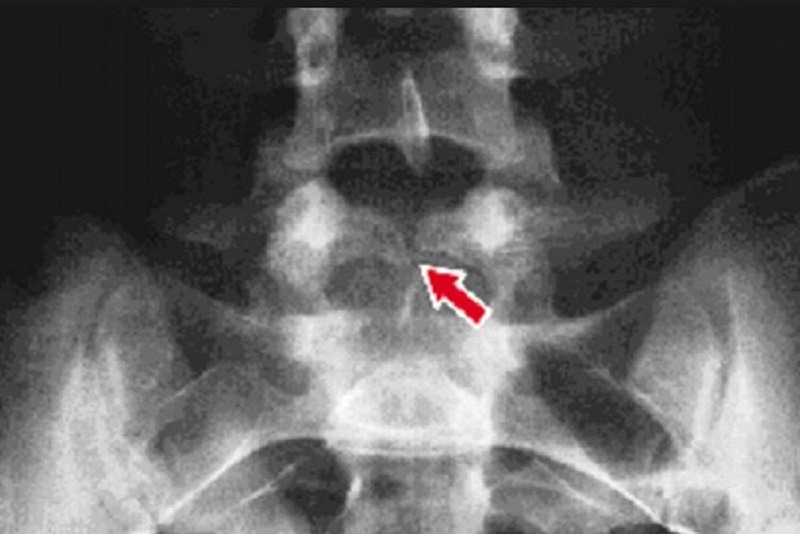

Gai đôi cột sống, còn được biết đến là tật nứt đốt sống, thường xuất hiện ở vùng cột sống thắt lưng.

Dựa trên nghiên cứu, các vị trí dễ xuất hiện gai đôi cột sống nhất là vùng đốt sống thắt lưng L5 và xương cùng S1. Dấu hiệu nhận biết ngoài đau nhức ở vùng xương sống ra thì bệnh không có bất kỳ triệu chứng đặc biệt nào.